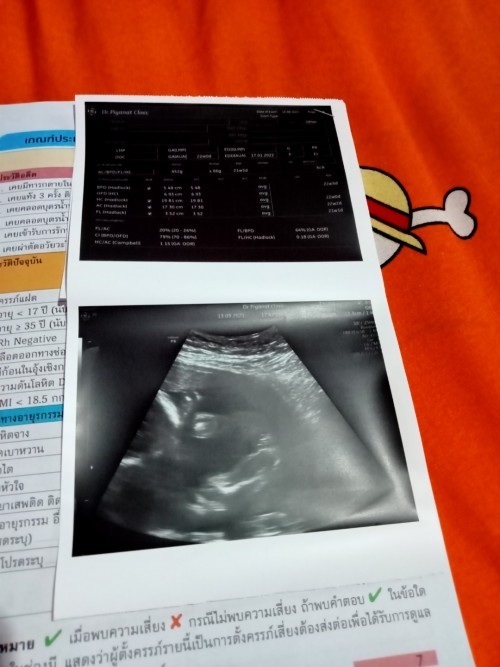

ท้องแรกค่ะยังไม่รู้เพศ 19สัปดากับ2วัน